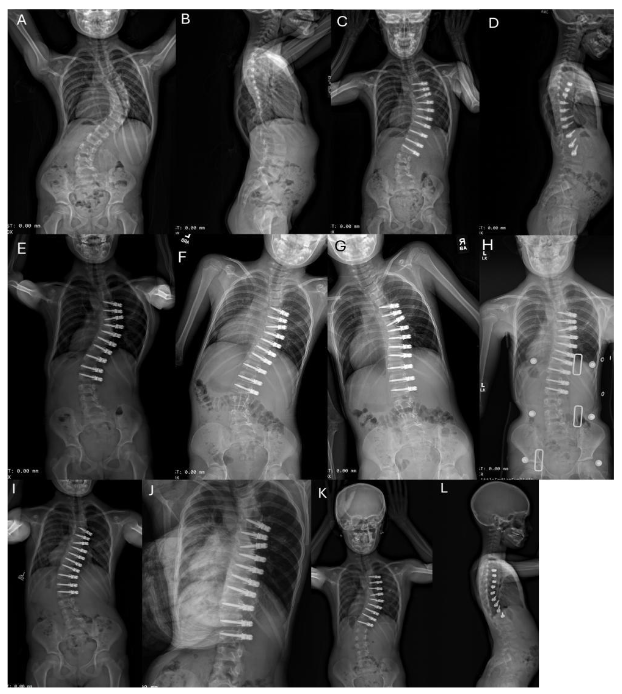

Within the cohort, 11 of the 15 patients underwent a secondary surgical procedure at an average interval of 43 months (range 23 to 77 months) following the index procedure. Return to the operating room for lengthening due to overcorrection occurred in 3/15 patients (20%). See Figure 2.

3.5 CASE HISTORY FOR FIGURE 2

Example of a unilateral thoracic ASC with intervertebral de-tethering releases needing lengthening for overcorrection at 29 months postoperative. Preoperative PA (A) and lateral (B) radiographs of a 5½-year-old girl with an idiopathic thoracic curve measuring 80°. The patient underwent right T5 to L2 ASC with single screw-line, double cord construct and 5 level intervertebral de-tethering releases (T7–T12).

Erect PA (C) and lateral (D) radiographs at 6 weeks postoperative: the instrumented Cobb angle measures 36°. Erect PA (E) at 16 months showing 20° of distal overcorrection from T11 to L2. Right supine bending radiograph (F) at 16 months postoperative shows intra-construct flexibility from 35° to 20° (T5 to T11). Left supine bending radiograph (G) of the lumbar curve at 16 months postoperative shows intra-construct flexibility from -20° to -10° (T11 to L2). (F) and (G) demonstrate preserved mobility and the ability to delay surgical release the cord. (H) PA radiograph of the patient in a night brace to delay cord lengthening revision. She refused to wear the brace after 6 months. (I) At 29 months postoperative (pre-revision), the maximum curve measures 35° from T4 to T10 and minus 45° from T10–L12. (J) The left fulcrum bend Cobb angle measures 1° from T11 to L2, demonstrating continued flexibility. Revision involved removal of distal instrumentation in L1–L2 and the addition of all new cords from T4 to L2 and 9 intervertebral de-tethering releases. Specifically, the construct has slack between the screws to allow for growth and curve correction.

Most recent PA (K) and lateral (L) radiographs at 6 weeks post revision (30 months after index procedure) measure 27° instrumented curve and 45° maximum curve. The patient is now 8 years old. It is expected she will continue to grow and the curve will continue to correct. However, she still only has a single line construct, and it is possible that construct breakage and loss of correction could occur, requiring another stage of surgery.

Fig. 2A-L. Example of a unilateral thoracic ASC with intervertebral de-tethering releases needing lengthening for overcorrection at 29 months postoperative. See Section 3.5 Case History for Figure 2.